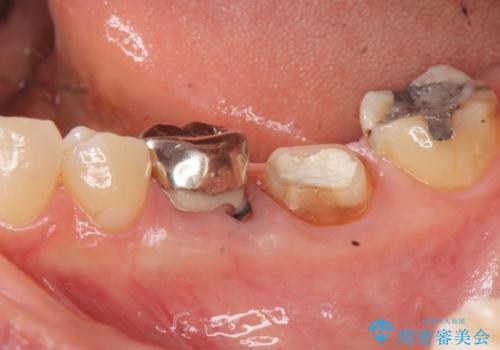

親知らずのせいで隣の歯が虫歯に 40代男性

歯並びや奥歯の痛み 色々と治したい 総合歯科診療

インプラント治療・セラミック治療を含む 全顎的虫歯治療

担当医 大元洋佑